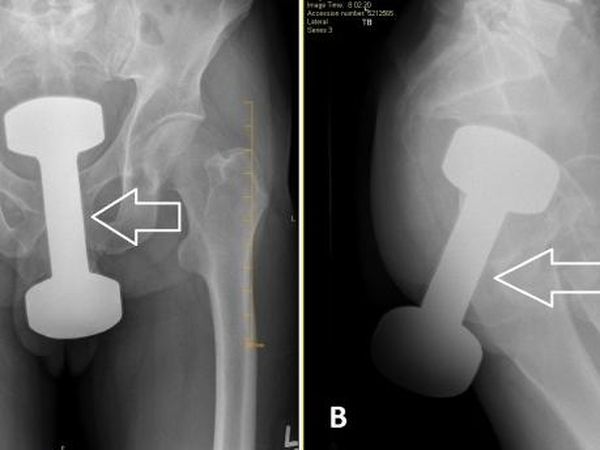

Berikut ini sederet temuan benda asing dalam anus yang bikin heran dokter. Ada dumbell gym seberat 2 kg, hingga bidet toilet.